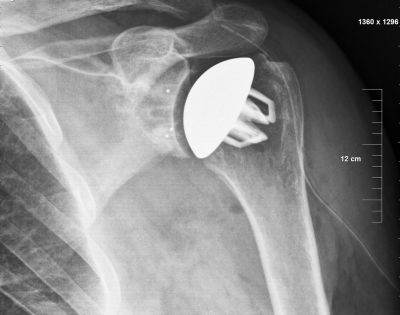

Сложна операция на раменна става на 45-годишен пациент, страдащ от множествена склероза, бе извършена в понеделник, 20 октомври, в Отделението по ортопедия и травматология на Университетската болница „Св. Марина” във Варна, съобщиха от здравното заведение за Moreto.net. Главата на раменната кост, съществена част от която е липсвала, е била заместена с изкуствена. Интервенцията се налага след безуспешна операция, която пациентът претърпява в друго здравно заведение. Реконструкцията на рамото бе извършена от екип специалисти от отделението с участието на д-р Борис Поберай, словенски раменен хирург, доскорошен президент на Секцията по раменна хирургия на Европейската асоциация по артроскопска и спортна хирургия.

Преди една година пациентът получава пристъп, вследствие на което изкълчва рамото си. Силната болка и ограничените до минимум движения не отминават след първата операция, на която се подлага. Благодарение на новата става, която му поставят в УМБАЛ „Св. Марина” във Варна, пациентът ще може отново да води пълноценен активен живот и дори да практикува любимия си спорт – плуване.